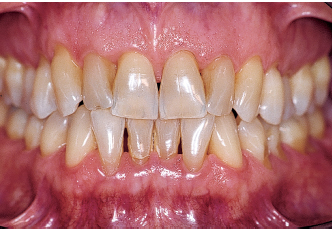

Fig 1-1a Aggressive periodontitis in a 40-year-old woman who is subject to stress and smokes one pack of cigarettes a day. The patient experienced an emotional shock 5 years earlier. A conventional treatment plan was initiated and included periodontal surgery throughout all quadrants. Professional maintenance (scaling and root planing) was carried out every 3 months, and the patient responded well.

Fig 1-1b Four years after treatment and maintenance therapy. Periodontal status has deteriorated in all areas. Observe the new attachment losses, dental migrations, and larger diastemata. It is clear that periodontal disease is not controlled. This patient’s disease was refractory to conventional treatment. Specific risk factors in this patient were underestimated.